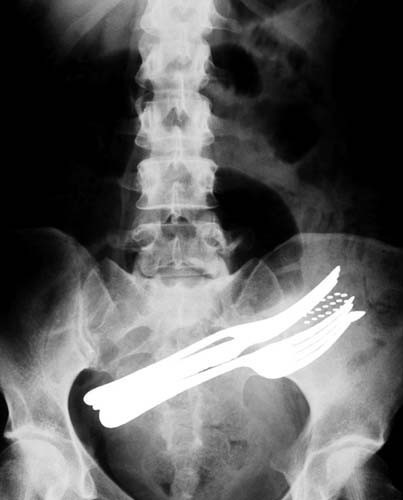

İki çatalı, bir tükenmez kalemi ve diş fırçasını yutmuş bir hasta. Bir erkeğin orta işaret parmağı ve orta parmak kemiklerine saplanmış bir çivi. Tarihten bir röntgen filmi. Bir askerin ayak parmaklarının arasına saplanmış bir kurşun. 7 yaşında bir çocuk tarafından yutulmuş anahtar... Yutulan jilet ve kaşık hastanın bağırsağına yerleşmiş Çengelli iğne bir kadının yemek borusunda... 60 yaşında bir şizofreni hastası, bronşlarındaki yabancı bir cisim. Bir hastanın ayağına saplanmış çatal... Jilet yutmuş bir akıl hastasının röntgeni... Bıçaklı bir saldırgan tarafından parmağı koparılmış bir kurbana ait röntgen. Yine bir hasta bir çatala basmış... Göğüs kafesine saplanmış bir bıçak Göğüse saplanmış bir kurşun Yutulmuş bir diş fırçası